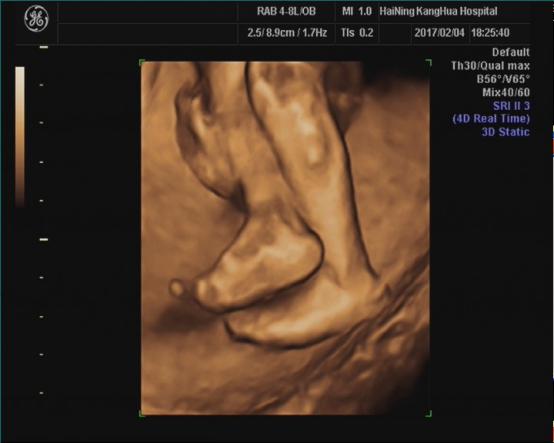

海宁康华医院“胎儿三维彩超检查”,为您创造“透视”条件!

胎儿三维超声检查最佳时间:

22—24周(备注:双胎不做三维超声检查)